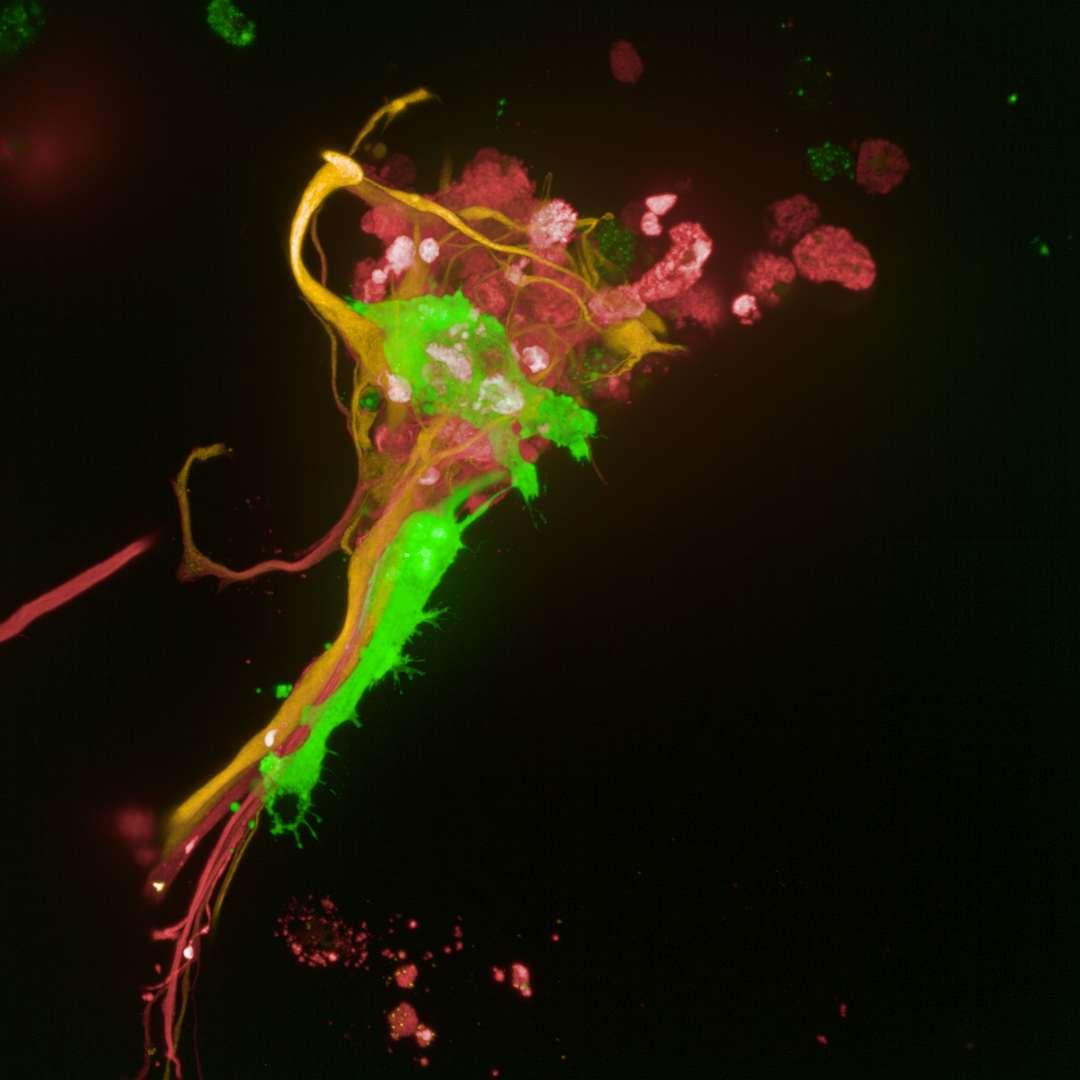

LPSandAβ42inducedmicroglia-dependentIL-6release.LPS+NigericintriggeredarobustIL-1βsecretionwhich isconsistentwithinflammasomeactivation.ThereisnodetectableIL-6inLPS-stimulatedcultureslackingmicroglia confirmingmicrogliaasaprimarysourceofinflammatorycytokines. Usingimmunocytochemicalmethodsandconfocalimaging,weobservedmicroglia(GFP)incloseproximityofneurons (β3-tubulin)andastrocytes(GFAP).

•WehaveestablishedaCNStriculturemodelinwhich microgliaareinvadingthegelandmigratingtowards neuronsandastrocyte.

•Usingdifferentstimuli,wehaveshownthat3DCNStriculturescanserveasamodeltoinvestigate neuroinflammation.